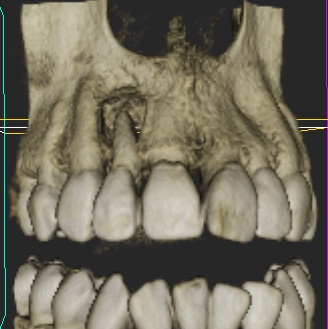

A female patient was referred for implant replacement of her failed upper right lateral incisor tooth. The tooth exhibited grade III mobility and had drifted forwards and downwards.

Clinical and CT scan assessment confirmed that the UR2 suffered from extensive bone loss with complete loss of the labial plate and was associated with a large periapical lesion which extended palatally and laterally towards the UR3. The UR3 tested positive to vitality testing.